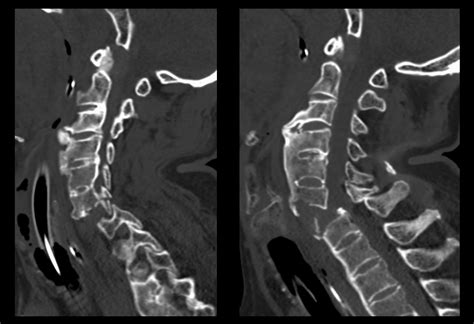

CT scans are often preferred over other imaging techniques, such as MRI, when quick and detailed information about bone structures is needed. This is especially important in emergency situations, such as after a traumatic injury, where immediate diagnosis is crucial.

Radiologists look for signs of fractures, dislocations, and other abnormalities that could indicate a spinal injury or condition. For example, a fracture may appear as a break in the continuity of the bone, while a dislocation may show misalignment of the vertebrae.

• Fractures: These can range from minor cracks to severe breaks that disrupt the integrity of the bone.

• Dislocations: These occur when the vertebrae are displaced from their normal position, often due to trauma.

Each of these findings has specific implications for treatment and management. For example, fractures may require immobilization or surgical intervention, while degenerative changes might be managed with physical therapy and medication.

• Multiplanar Reconstruction (MPR): This technique allows for the creation of images in multiple planes (axial, sagittal, and coronal), providing a more comprehensive view of the spine.